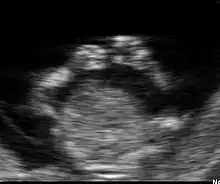

Fœtus à 12 semaines

Dans la plupart des cas, une échographie pratiquée à 12 semaines permet de détecter de nombreuses pathologies. Bien entendu, cette détection dépend de nombreux facteurs qui ne sont pas tous du ressort du médecin. Le surpoids et l'obésité sont actuellement les facteurs limitants les plus importants.

Sur la figure 7 on distingue à gauche une zone intra-abdominale blanche correspondant à l'intestin du fœtus. Dans cette zone blanche, une petite tache noire qui est la vessie. Enfin, à droite des intestins, on peut distinguer le foie et les poumons.